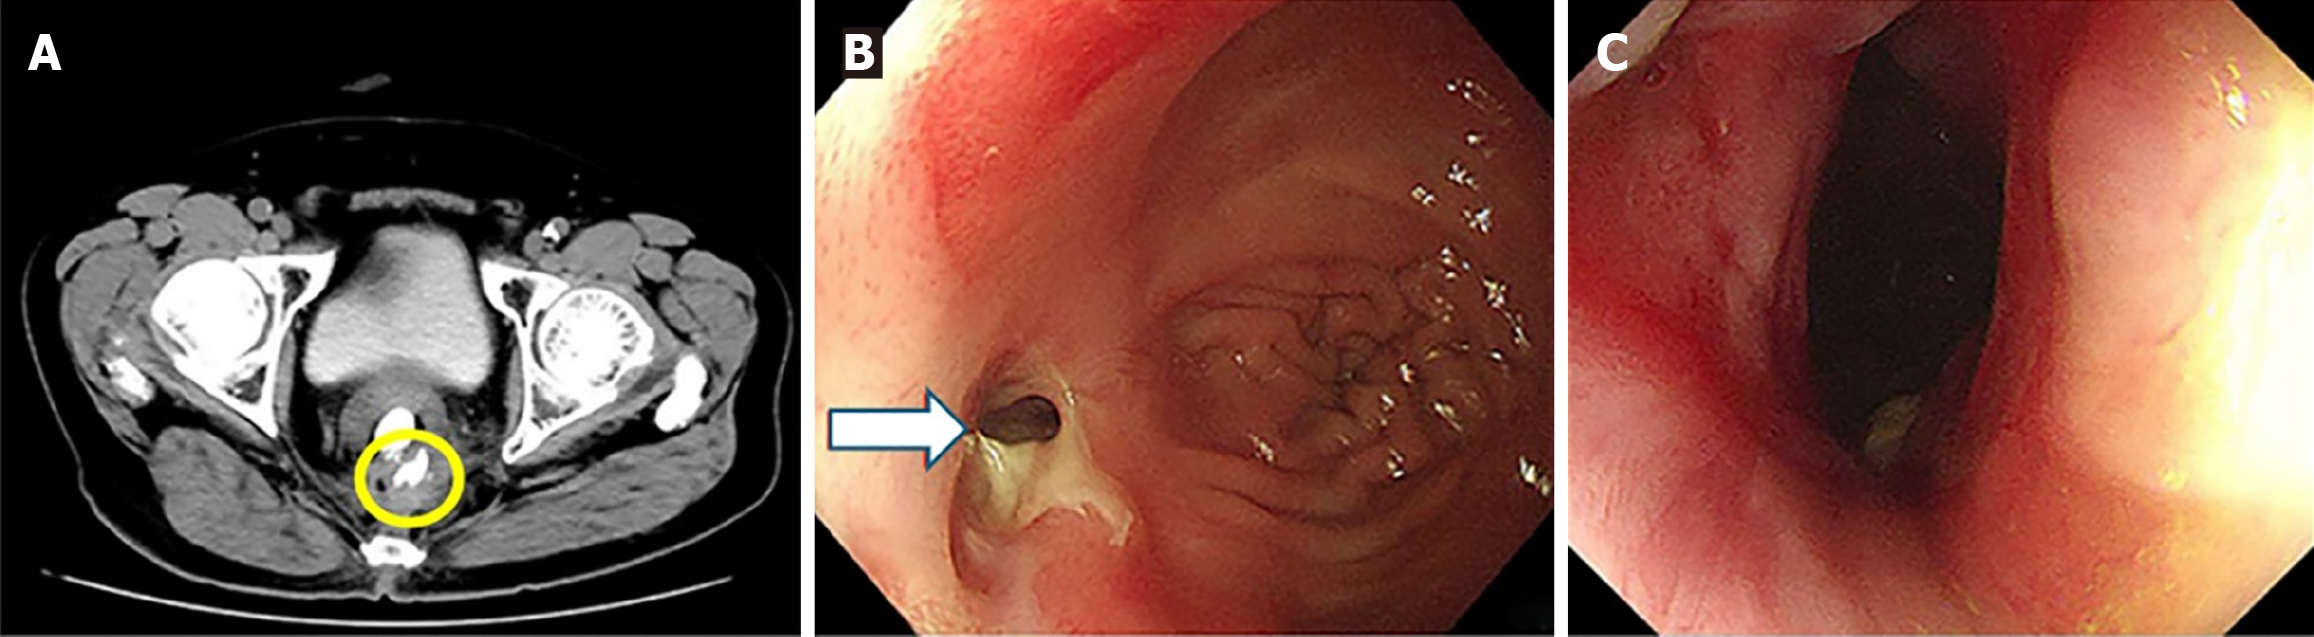

Case 1: Computed tomography (CT) scan revealed extraluminal contrast leakage outside the rectum (Figure 2A). Colonoscopy subsequently revealed a pin-hole defect in the rectal wall at the anastomotic site, confirming the presence of an anastomotic leak (Figure 2B). Following treatment, colonoscopic re-examination revealed an intact anastomosis exhibiting localized scar hyperplasia, with no evidence of mucosal depression or defect (Figure 2C).